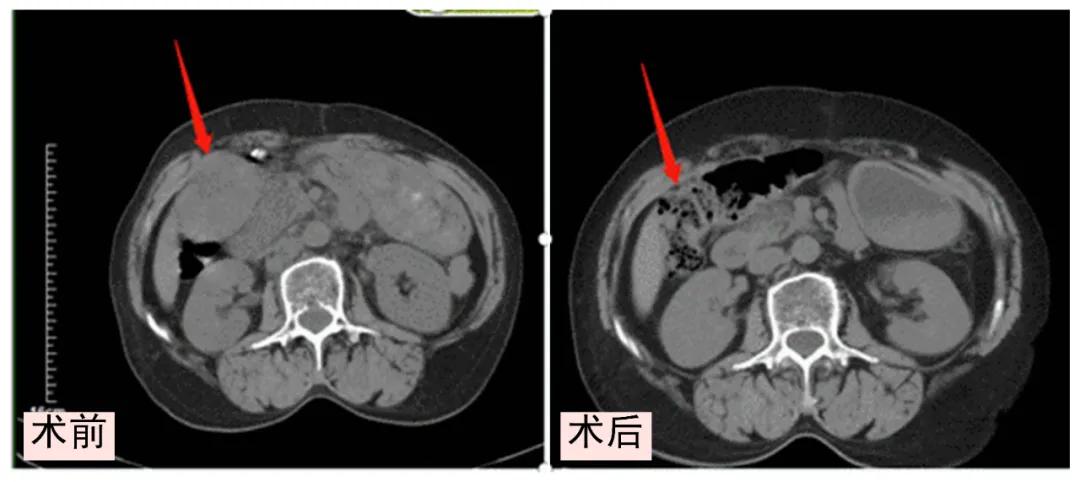

患者石女士,61岁,3年前因腹胀、腹痛、腹部肿块在当地医院完善相关检查后行手术治疗,术后病理显示:大网膜浆液性腺癌。患者于3月前再次出现腹胀、腹痛就诊于我院肿瘤科一病区,接诊医师张真真详细询问患者病情后,给予完善相关检查,CA125值明显高于正常值,CT结果显示:纵膈、肝门部、腹腔内、腹膜后多发肿大淋巴结。结合患者病史,考虑原发恶性肿瘤转移可能。在请示科主任王志伟并经科室全体医师讨论后,专家团队为患者进行原发大网膜浆液性腺癌针对性治疗和化疗。经过一段时间的精心治疗,可见肿物明显缩小,且肿瘤标志物逐渐降低,CA125值也逐渐降至正常。患者现已康复出院,患者及家属对肿瘤一病区的医护人员表示感谢。